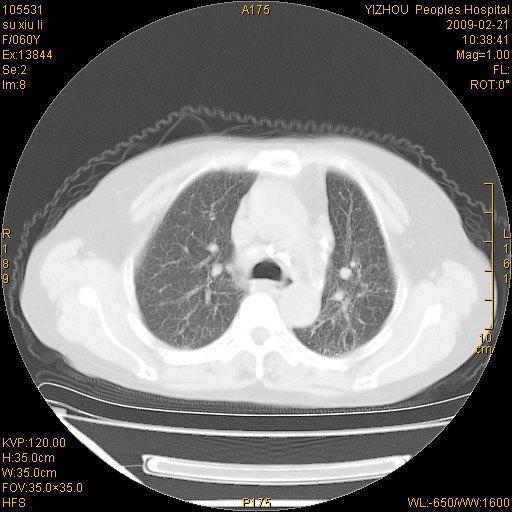

标题: CT18259:两肺间质纤维化?

女,60岁,反复咳嗽1月。

两肺支扩,以肺为著合并双肺较广范纤维化病变。建议除外结核等病变。

两下肺支扩

符合间质感染,部分纤维化表现

特发性间质纤维化

特发性间质纤维化伴支扩!